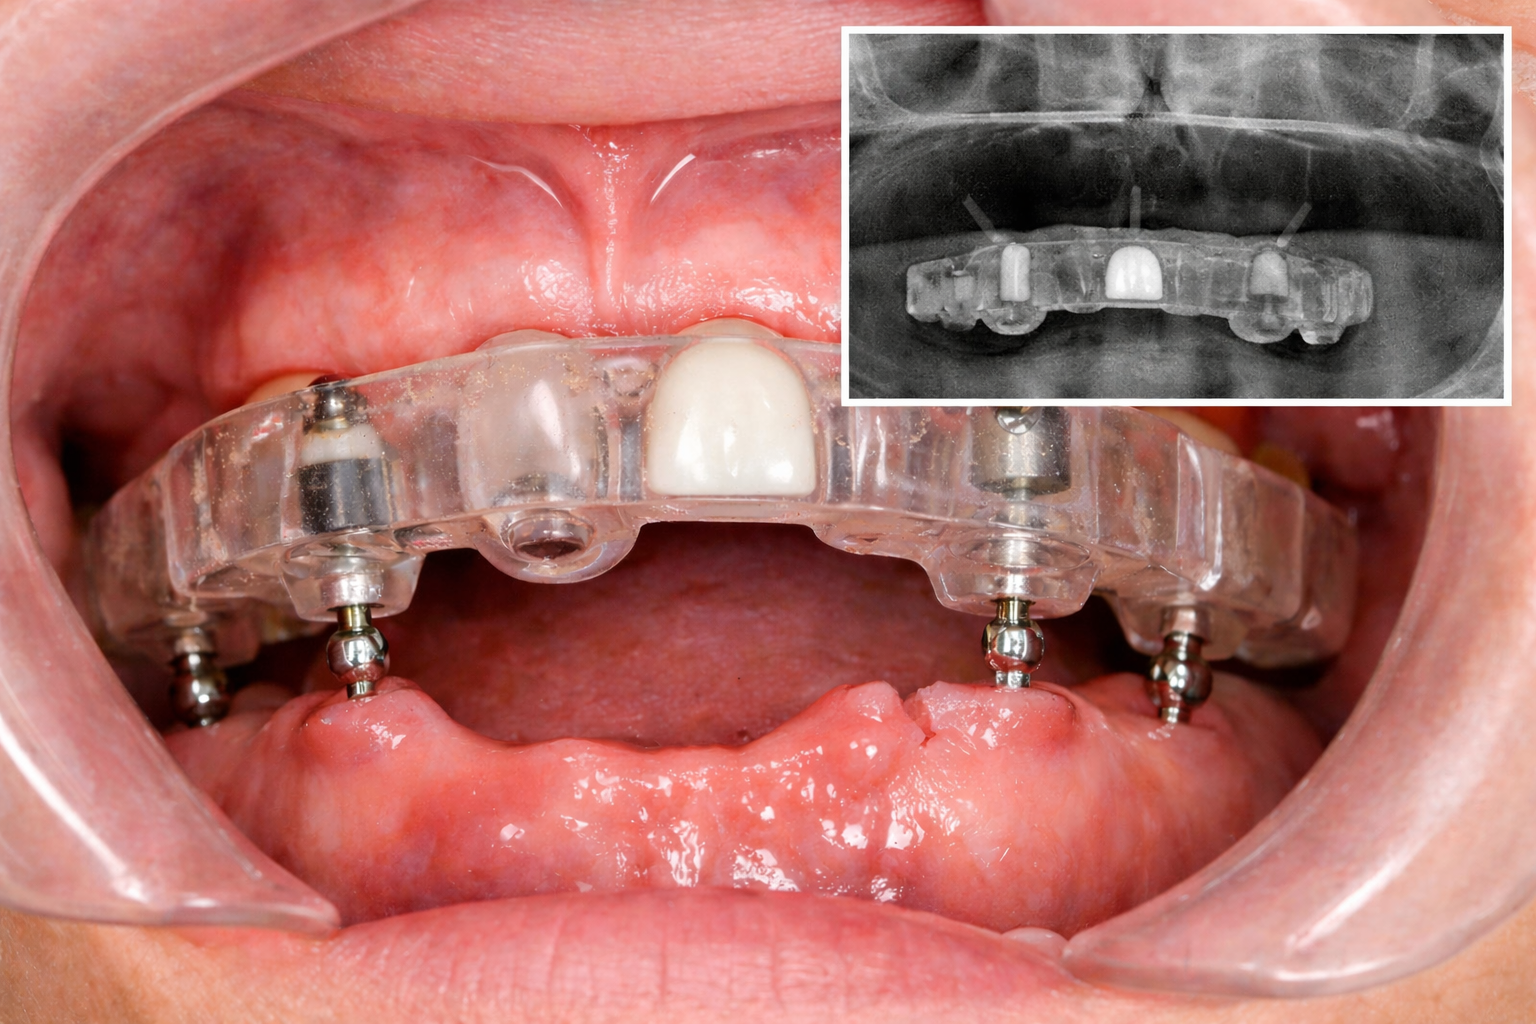

В качестве анатомических ориентиров для повышения точности часто используют мини-имплантаты. Они выполняют двойную роль: стабилизируют хирургический шаблон в полости рта и служат реперными точками (сканмаркерами) для калибровки цифровых снимков. Для сканирования применяют рентгенологические шаблоны с рентгеноконтрастными маркерами (гуттаперча, искусственные коронки, композиты), которые могут быть изготовлены специально или добавлены в существующий протез пациента.